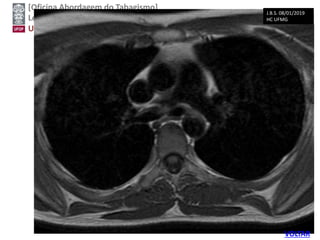

J.B.S. 08/01/2019

HC UFMG

VOLTARUSPSTF, 2014

Screening Tests

Low-dose computed tomography has shown high

sensitivity and acceptable specificity for the

detection of lung cancer in high-risk persons.

Chest radiography and sputum cytologic

evaluation have not shown adequate sensitivity or

specificity as screening tests. Therefore, LDCT is

currently the only recommended screening test for

lung cancer.

USPSTF, 2014